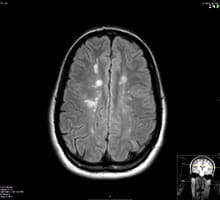

An MRI image showing a long area of inflammation in the spinal cord of a patient with NMO

An MRI image showing a long area of inflammation in the spinal cord of a patient with NMO.

Neuromyelitis Optica (NMO) or Devic’s disease is a severe autoimmune inflammatory condition that preferably involves the optic nerves and the spinal cord causing extensive inflammation and tissue damage. It is caused by specific antibodies against water channels in the central nervous system and often leads to significant disability if not treated aggressively and in a timely manner. NMO is more common in African American and Asian populations and is not uncommonly misdiagnosed as MS which can lead to improper and potentially harmful treatment. Learn more about Neuromyelitis Optica.

An MRI image showing a long area of inflammation in the spinal cord in a patient with NMO.